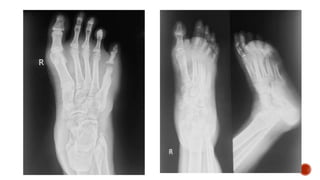

 Dorsoplantar radiograph of the foot shows destruction of the head of the 5th

metatarsal and the base of the proximal phalanx of the 5th toe with apparant

widening of teh joint space.

 Foot radiograph :

 Dorsoplantar: metatarsals in neutral position

 Medial: DP projection with the foot angled 30-40° medially

 Lateral

 Weight bearing